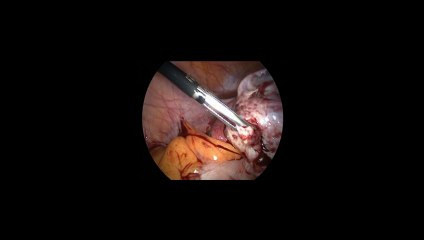

Laparoskopi ile Endometiroma 32 - Prof. Dr. Aydan Biri

Laparoskopi ile Endometiroma 32 - Prof. Dr.